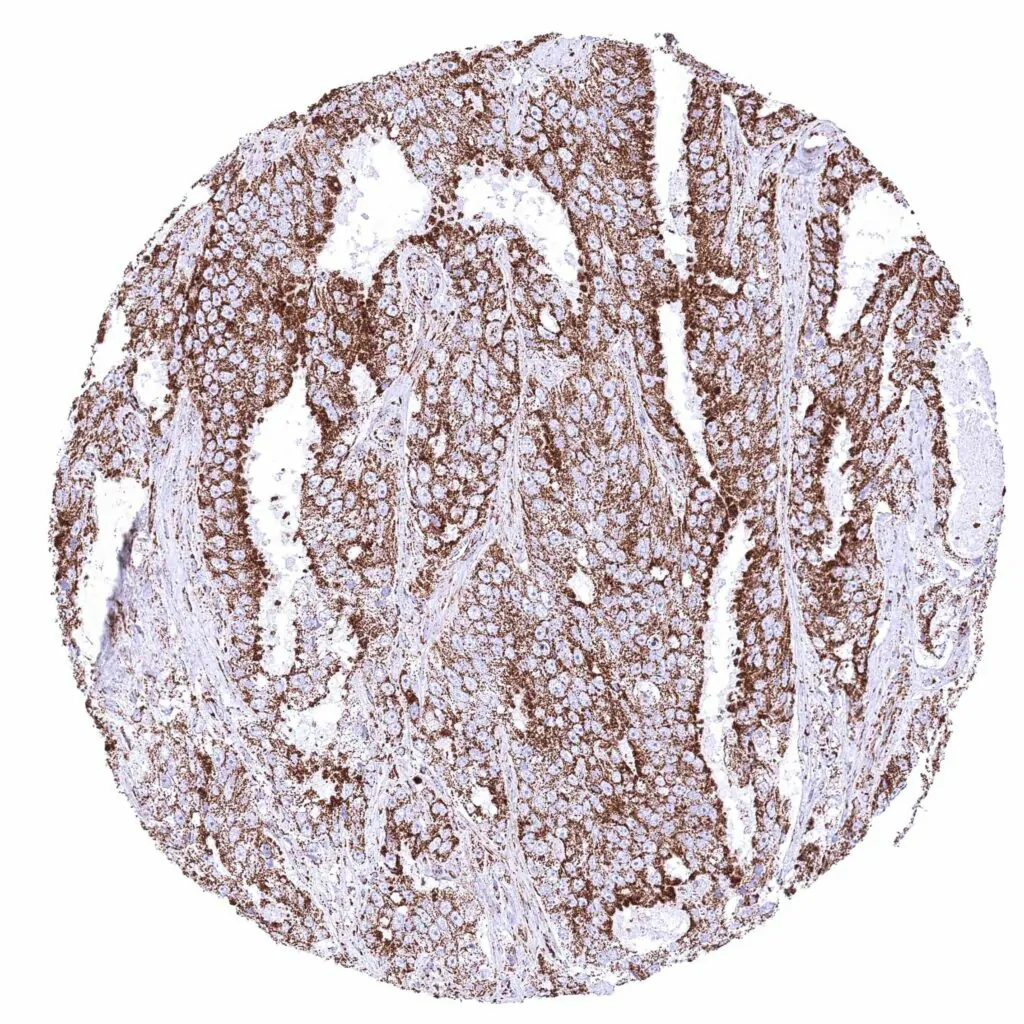

Colon – Colorectal adenocarcinoma with strong cytoplasmic ATP5J staining of all tumor cells.